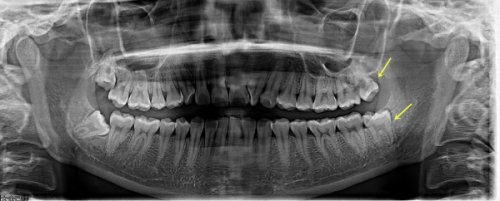

沈阳馨格口腔门诊部有不少特色项目。其中,超声波洗牙是其一大特色。医生洗牙技术娴熟,注重卫生,洗牙过程舒适,没有疼痛感,还会细心为患者讲解科普知识,以及回家后如何正确刷牙等注意事项。另外,种植牙项目也值得一提,该门诊部开设的微创种植牙技术优势明显,单颗缺牙从种牙开始到结束大概需要20分钟即可完成手术,伤口小,术后容易修复,这对医生的种牙技术要求极高。